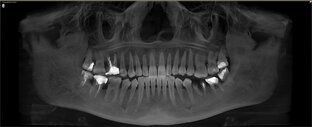

Конец ноября 2024 года, ко мне приходит пациент по рекомендации от доктора терапевта. Расстроенный, потерянный, не понимает что ему делать и как дальше жить… Я постарался успокоить его и сказал, что всё решаемо, не переживайте. И начал слушать историю, которую он мне поведал... Краткая предыстория: лечился в другой клинике. Сверху сделали операцию было всё ок. Потом, через некоторое время начали делать снизу похожую работу на 4-х имплантатах (пациент попал по какой-то причине к другой команде докторов в этой же клинике) и что-то пошло не так в лечении...